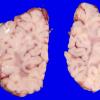

Familial erythrophagic lymphohistiocytosis (4)